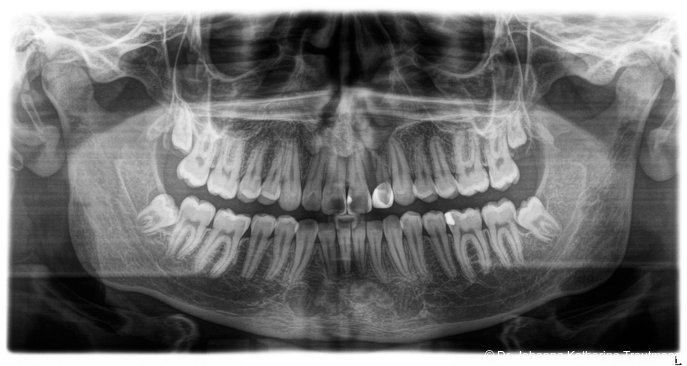

Das Fernröntgenseitenbild zeigte eine skelettale Klasse IIAnomalie mit einem Wits von 5,6 mm, bei einer tiefen Konfiguration (ML NL = 16,5°) mit bialveolär retrudierten Fronten (OK1NA = 5,9°; UK1NB = 10,4°), was sich auch in der Modellanalyse widerspiegelte. Hier zeigte sich zudem ein schmaler Oberkiefer mit multiplen Kippungen und Rotationen in der Front, einem hypoplastischem 22 sowie einer Mesialwanderung des 16. Des Weiteren zeigte sich eine asymmetrische Bisslage mit 1 PB distal rechts und ½ PB distal links bei einem Overjet von 2,5 mm sowie einem Overbite von 5 mm. Während im Unterkiefer bereits die zweite Zahnwechsel phase begonnen hatte, zeigte sich im Oberkiefer noch kein Wechsel in den Stützzonen. Gerade bei Patienten mit Spaltbildungen ist eine engmaschige Überwachung des Durchbruchs der oberen Eckzähne essenziell. Während bei der Allgemeinbevölkerung die Prävalenz von verlagerten Eckzähnen bei ca. 2,8 Prozent liegt2, ist diese bei Patienten mit Lippen-Kiefer-Gaumen-Spalten um den Faktor 10 erhöht.3, 4 Als klassische Risikofaktoren gelten zudem Platzmangel, transversale Enge aber auch Fehlstellungen, Nichtanlagen oder Hypoplasien der zweiten Schneidezähne. Diese übernehmen normalerweise die Funktion der Leitschiene für den S-förmigen Durchbruch der Eckzähne. Im vorliegenden Patientenfall kommen also mehrere Risikofaktoren für eine Verlagerung zusammen, was die rechtzeitige Diagnostik zur Abklärung einer Durchbruchsproblematik rechtfertigt. Da im Spaltbereich auch zusätzlich ein ausgeprägtes Knochendefizit vorliegen könnte, sollte auch immer die Option einer sekundären Osteoplastik abgewogen werden, deren Indikation und Timing optimal zum Durchbruch der Canini angepasst werden sollte.5

Zur genaueren Diagnostik der Lage beziehungen der Eckzähne und des Knochenangebotes im Spaltbereich kann neben den kieferorthopädi schen diagnostischen Unterlagen laut der S2 kLeitlinie Dentale digitale Volumentomografie6 auf eine dreidimensionale Bild gebung zurückgegriffen werden. In dieser zeigte sich eine vestibuläre Verlagerung des 13, eine palatinale Verlagerung des 23, sowie ein deutliches Knochendefizit im Spaltbereich mesial des hypoplastischen 22 (Abb. 2). Nach Auswertung der 3D-Daten erschien aufgrund der palatinalen Lage des 23 eine invasive Operation wie eine sekundäre Osteoplastik keinen entscheidenden Vorteil für die weitere Be handlung zu haben. In Rücksprache mit der Mund-Kiefer-Gesichtschirurgie der UMG wurde daher auf die OP verzichtet und initial die kieferorthopädische Therapie in den Vordergrund gestellt.

Positiv hervorzuheben ist hingegen der er zielte Knochen erhalt beziehungsweise der partielle Attachmentgewinn im Bereich der Spalte. Wie sich in den Verlaufskontrollen der OPGAufnahmen erkennen lässt, führte die Bewegung der Zähne 21 und 22 in den Spaltbereich zu einer deutlichen Verbesse rung der knöchernen Situation. Obwohl das Knochenniveau nicht vollständig physiologisch ist, konnte ohne zusätzliche Knochenaugmentation eine stabile Knochen und Gewebesituation erreicht werden. Dass ein Attachmentgewinn durch gezielte kieferorthopädische Zahnbewegung möglich ist, wurde bereits von Melsen et al.22 beschrieben. Während sich die meisten nachfolgenden Studien auf parodontal vorgeschädigte Gebisse konzentrierten, zeigt der vorliegende Fall eine mögliche Übertragbarkeit dieser Mechanismen auf Spaltpatienten mit moderatem Knochendefizit.